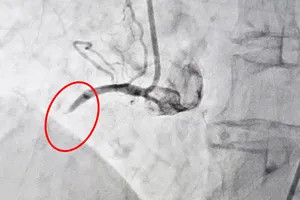

Lần đầu tiên đặt stent điều trị bệnh hẹp động mạch cảnh tại bệnh viện tuyến quận Y tế - Sức khỏe 05/07/2017 12:18